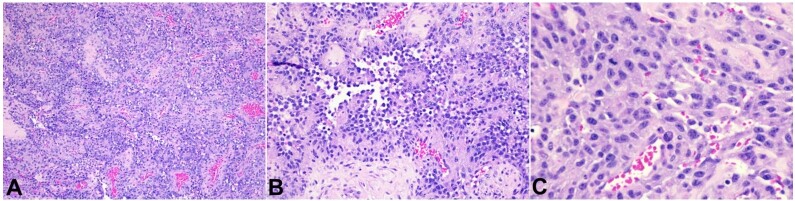

原发性心脏肿瘤很少见。心脏肉瘤是最常见的恶性心脏肿瘤。这些肿瘤的预后很差,总生存期中位数为 25 个月。临床特征包括呼吸困难、心律失常、心包积液、心力衰竭和心脏性猝死。诊断通常具有挑战性。因此,对于标准疗法无效的非典型表现,除了临床高度怀疑外,心脏成像检查也起着重要作用。超声心动图、计算机断层扫描和心脏磁共振成像对确诊至关重要。手术、化疗和放疗等多模式治疗比单独使用其中任何一种模式都能提高疗效。我们描述了一例感染 COVID-19 的 30 岁男性患者的病例,该患者反复出现出血性心包积液,标准治疗无效,最终在活检发现诊断结果并使用 PET-CT-FDG 扫描进行分期后被确诊为心包血管肉瘤。我们的病例再次强调了在发病早期考虑恶性病因的重要性,尤其是在炎性细胞学诊断为积液的情况下,仍反复出现出血性积液时。它还强调了心脏 CT 和 MRI 在确定位置和扩散情况以及计划进一步治疗方案中的重要地位。如果早期诊断,采用多模式方法可延长估计的存活时间。

Primary cardiac tumors are rare. The cardiac sarcomas are the most common malignant cardiac tumors. These tumors have a dismal prognosis with an overall median survival of 25 months. Clinical features include dyspnea, arrhythmias, pericardial effusions, heart failure, and sudden cardiac death. The diagnosis is often challenging. Therefore, the cardiac imaging workup plays a central role in addition to a high clinical suspicion in the setting of atypical presentations that do not respond to standard therapies. The echocardiography, computed tomography, and cardiac MRI are crucial in clinching the diagnosis. Multimodal treatment with surgery, chemotherapy, and radiotherapy has been shown to improve outcomes, as opposed to using either of these modalities alone. We describe the case of a 30-year-old gentleman with COVID-19 infection who developed recurrent hemorrhagic pericardial effusions refractory to standard treatment and was eventually diagnosed as a case of pericardial angiosarcoma after his biopsy revealed the diagnosis and staging was performed using PET-CT-FDG scan. Our case re-emphasizes the importance of considering a malignant etiology early in the course of the disease presentation, especially in recurrent hemorrhagic effusions despite an inflammatory cytologic diagnosis of fluid. It also highlights the place for cardiac CT and MRI to ascertain the location and spread and to plan the further course of treatment. If diagnosed early, the estimated survival time can be prolonged by instituting a multimodal approach.